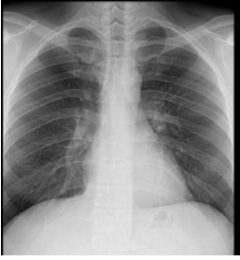

What is this and what type of scan

PA CXR

Label this CXR (10 things)

1) trachea 2) hilum- should have R and L 3) lungs 4) diaphragm 5) heart 6) aortic knuckle 7) ribs 8) scapulae 9) breasts 10) bowel gas